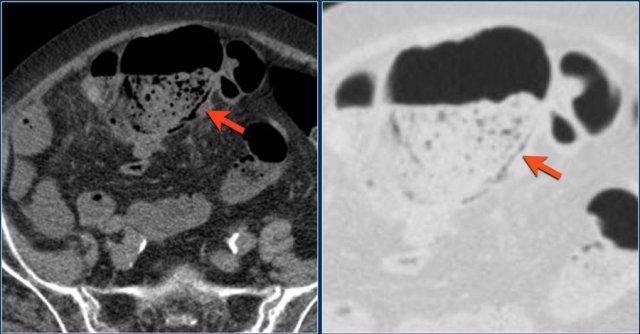

Đây là hình ảnh bệnh nhân thiếu máu cục bộ ruột do huyết khối tĩnh mạch mạc treo tràng trên – SMV (mũi tên đỏ).

Lưu ý tình trạng ứ máu tĩnh mạch trong mạc treo ruột (mũi tên vàng).

Đây là một bệnh nhân khác bị thiếu máu cục bộ một đoạn dài ruột non do tắc ruột quai kín.

Một đặc điểm hình ảnh quan trọng của tắc ruột quai kín là hình ảnh các quai ruột non giãn xếp theo kiểu nan hoa bánh xe với các mạch máu mạc treo hội tụ về một điểm trung tâm.

Các dấu hiệu thiếu máu cục bộ trong tắc ruột quai kín tương tự như ở các bệnh nhân có nguyên nhân thiếu máu cục bộ mạc treo khác:

- Dày thành ruột

- Phù nề mạc treo ruột

- Cổ trướng

- Sự ngấm thuốc của thành ruột trong thiếu máu cục bộ có thể bình thường, tăng do hiện tượng tái tưới máu, hoặc giảm/mất ngấm thuốc như trong trường hợp này.